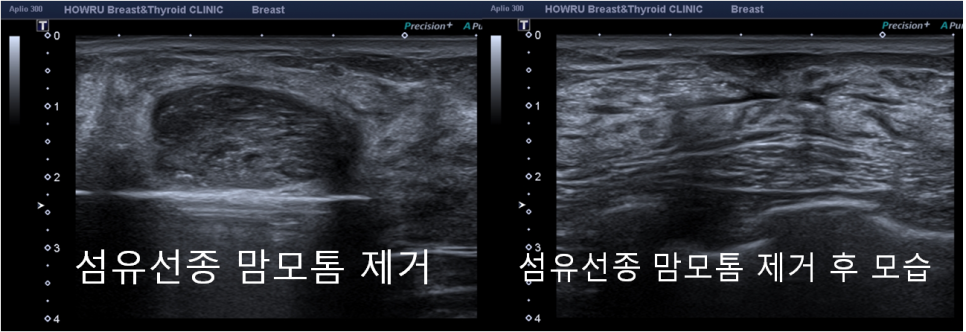

그러나 방이동외과에서는 섬유선종이 크기가 크거나 피부에 가까이 위치한 경우, 가슴 보형물 근처에 발생한 경우, 통증을 유발하거나 유방의 미용적인 면을 해치는 경우에 맘모톰 수술로 제거를 고려해 볼 것을 안내해 드리고 있습니다.

방이동외과에서는 섬유선종 맘모톰 수술을 진행할 시 고분별능 초음파 검사를 통해 피부와 얼마나 가까운 위치에 자리 잡아 있는지 확인합니다. 이후 피부와 가까운 거리에 위치해 있다면 국소마취제를 주입하여 안전 공간을 확보한 후 주변 조직의 큰 손상 없이 맘모톰 수술을 마무리합니다.

연세하와유외과의 장비는 최신 업그레이드 맘모톰 리볼브 EX를 이용하기 때문에 보다 안전하고 효율적인 치료가 가능하다는 점을 참고해 주시기 바랍니다.